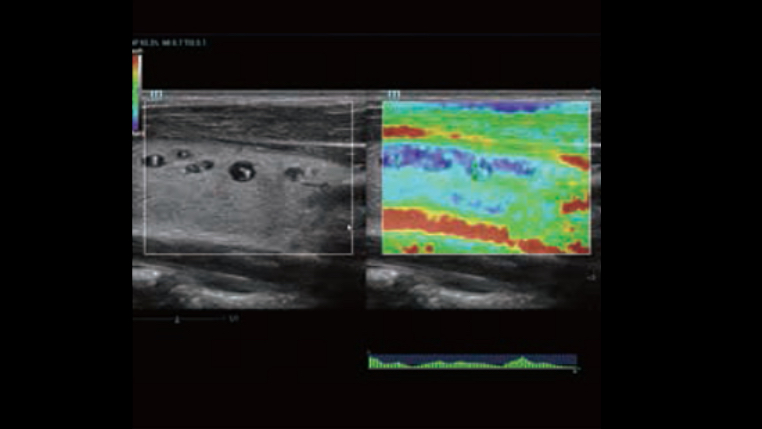

Channel data based ZST+ provides Enhanced Channel Data Processing for greatly improved imaging clarity. By multiple and retrospective channel data processing, it makes the best use of acoustic information for image improvement.

HD Scope: By processing channel data retrospectively, HD Scope enables tissue-specific enhancement with improved detailed information and image contrast on specific region of interest.